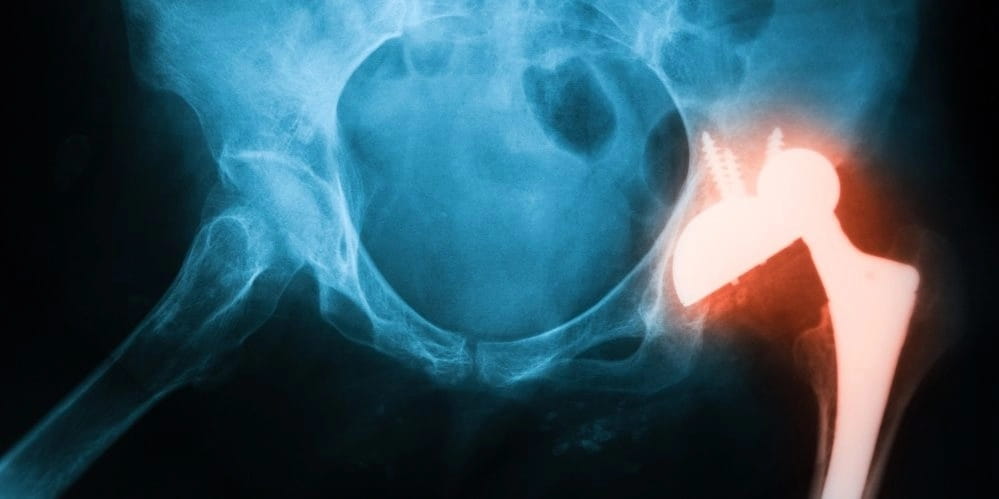

3. Перелом копчика

Перелом диагностируется несколько реже, чем ушиб, и является серьезным заболеванием. Боль развивается острая и, в зависимости от локализации перелома, может сохраняться в течение длительного времени или проходить через несколько дней после получения травмы. В такой ситуации пострадавший может не обратиться за врачебной помощью своевременно, и из-за этого болезнь будет только прогрессировать, что в результате приведет к появлению тяжелого осложнения, которое может даже стать причиной инвалидности. Болит в области копчика тогда постоянно.

image

Основными симптомами, которые появляются при переломе копчика, являются особенно сильная боль, отек, краснота в больной области, а также затруднения при ходьбе. Во многом перелом по проявлениям схож с ушибом, и потому для его диагностики обязательным является проведение рентгена.